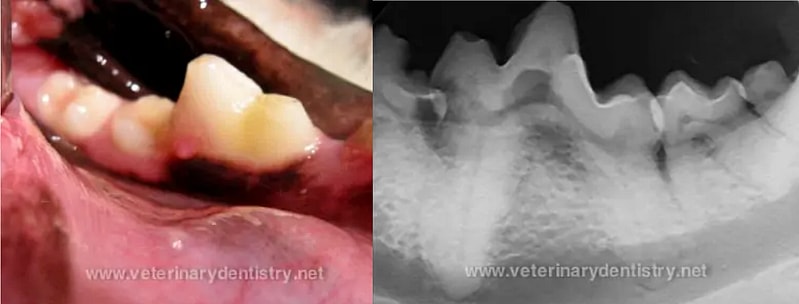

In this photo, we can see a pup with a gnarly snaggletooth. In this situation, the tooth was causing discomfort when the pup was chewing, so the tooth was drawn forward with a set of orthodontic braces.